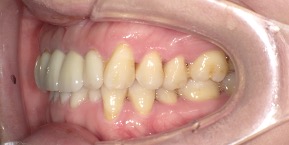

26歳女性のビフォーアフター

| 診断 | 空隙,叢生 |

| 治療方針 | 治療方針:前歯の咬合関係改善と空隙閉鎖を主な目的にて主にIPR(歯と歯の間をわずかに削合してスペースを獲得する方法)を組み込んだ動的矯正治療を行い、空隙、前歯咬合を改善後、保定を行う。臼歯部の咬合関係はプランの都合上維持することとした |

| 治療費 ※ | 69万8千円(診断、型取り、矯正中のメンテナンス、保定装置を含む料金) |

| 治療期間 | 1年8か月 |

| リスク | 1日20時間以上マウスピースを使用できない場合、歯が動かなかったり、想定しない誤差により不完全に終わる可能性がある。装着時や食事時に痛みを伴う。歯肉退縮や虫歯になるおそれがある。また、指導通りに装着できていない場合や適切なブラッシングが出来ていないとそのリスクが高くなる。歯根が短くなることがある。ごくまれに歯の神経が損傷してしまうことがある。過去にぶつけたり深い虫歯治療をしたことがあるとそのリスクはやや高くなる。矯正後には保定装置が必要。適切な使用ができない場合、後戻りの原因となる。将来的に歯並びが動いて再矯正が必要な場合がある。舌癖(舌で歯を押し出す癖)親知らずが正常に生えていない場合、その可能性がやや高くなる。 |